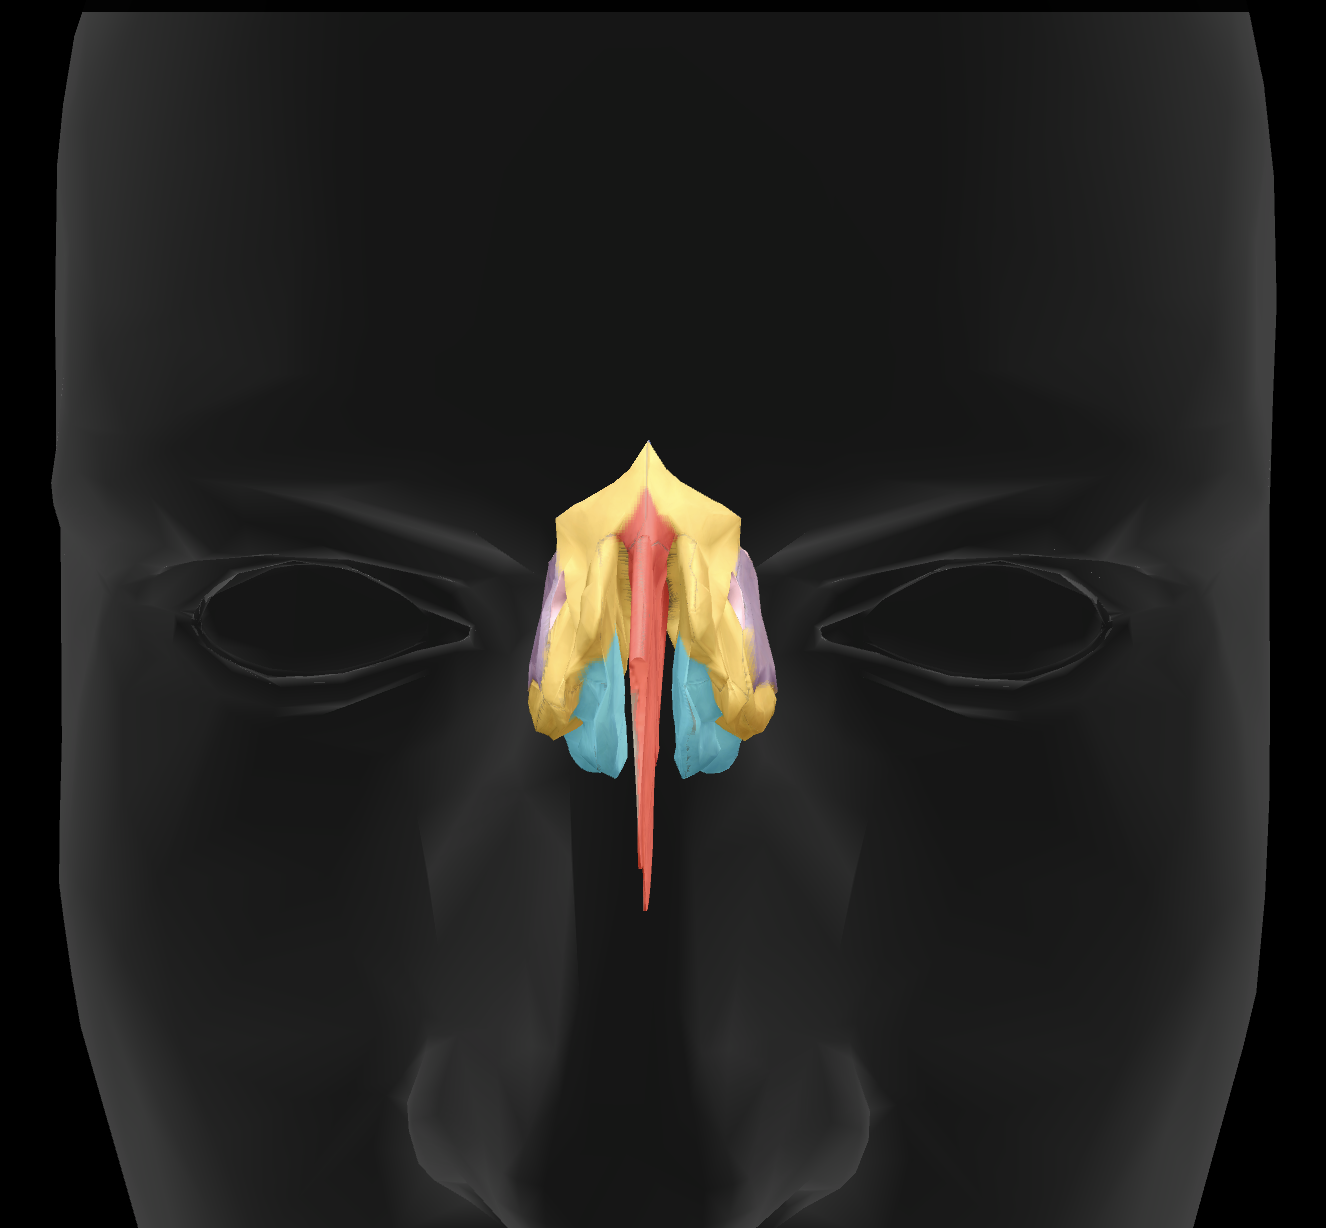

What features make up the nasal septum?

perpendicular plate of ethmoid bone and vomer

What is the name of this feature?

perpendicular plate

What is the name of this feature?

middle nasal conchae

What is the name of this feature?

superior nasal conchae